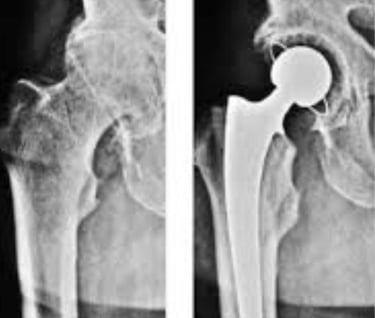

Šlaunikaulio galvos avaskulinės nekrozės procesas visada baigiasi klubo artritu. Sergant klubo artritu, šlaunikaulio galvos ir šlaunikaulio sąnarių paviršiai tampa netaisyklingi, prarandant sąnario judesį. Gydymo pasirinkimas yra bendras klubo sąnario pakeitimas.

Visiškas klubo sąnario endoprotezavimas – tai procedūra, kurios metu chirurgas pažeistą šlaunikaulio galvą ir pažeistą jungties paviršių pakeičia protezais. Pažeista šlaunikaulio galva pašalinama ir pakeičiama metaliniu stiebu ir kamuoliuku. Pažeista klubo sąnario lizdo kremzlė pakeičiama metaliniu lizdu.